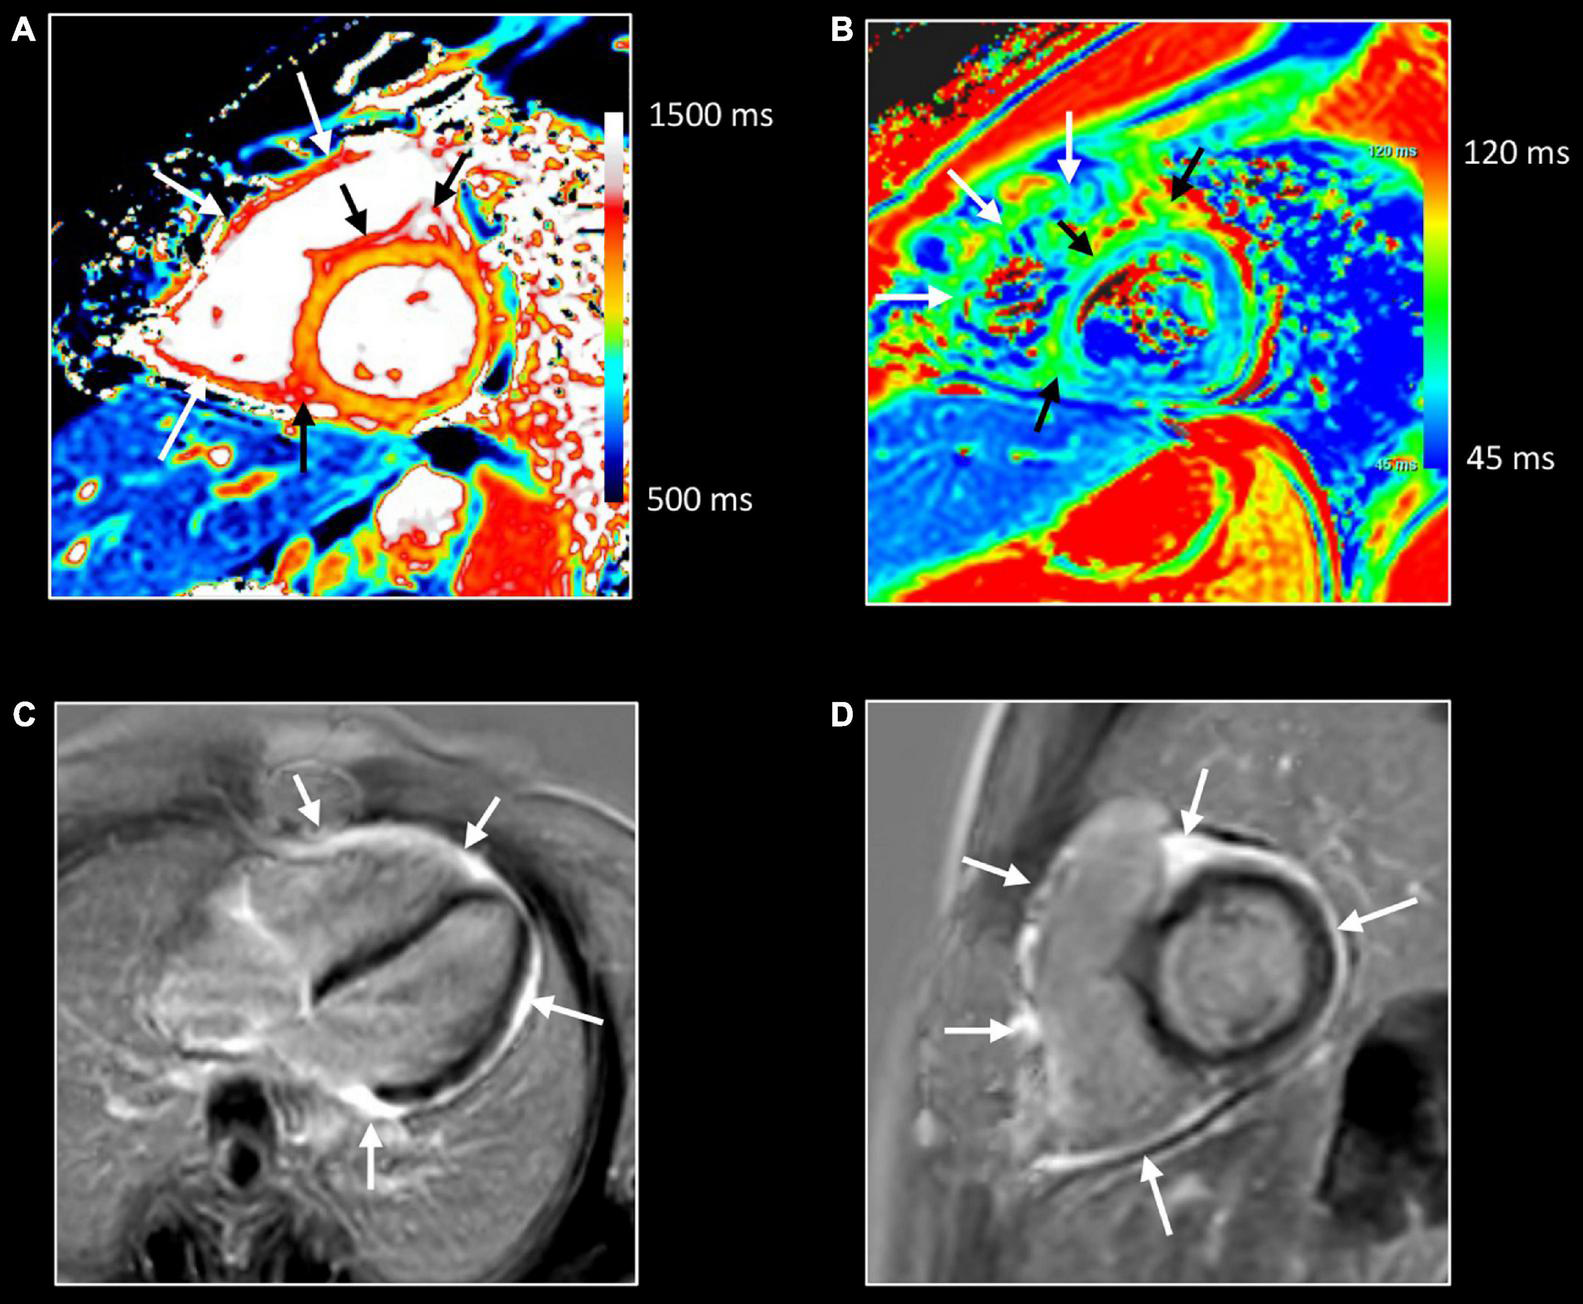

While depiction of diseased tissue using ‘weighted’ MRI sequences [i.e., T1w, T2w, early gadolinium enhancement (EGE) and LGE] relies on differences in SI with the surrounding, deemed normal, tissues, mapping techniques allow for the reconstruction of parametric maps of both T1 and T2 relaxation times on a pixel-by-pixel basis (Figures 1C–F, 2) (28). Consequently, drawing a region of interest (ROI), calculation of the local T1 and T2 relaxation times is possible. An in depth, discussion on the different T1 and T2 mapping sequences is beyond the scope of this review paper. However, it is important to understand that T1 and T2 relaxation times are also influenced by the magnetic field strength (both increase with higher field strength) and by the type of sequence used (29). These are important issues when interpreting T1 and T2 values, as they are not trivially interchangeable between machines/vendors/sequences. As most of the influencing factors can be standardized, age- and gender-corrected normal values (and cut-off values) for T1 and T2 can be determined, offering a truly quantitative approach on tissue characterization (30, 31). Thus, using similar scanning conditions, T1 and T2 relaxation times can be used to monitor disease progression (Figures 2, 3).

As mentioned above, the pixel-by-pixel relaxometry overcomes some limitations of SI-based techniques allowing the evaluation of both focal and diffuse tissue pathology. T2 Mapping—which is always acquired before contrast administration – is highly sensitive for tissue water (32). Abnormally increased T2 values reflect focal or diffuse tissue edema. Parametric T1 mapping is acquired before (native T1) and often after contrast administration. Native T1 values can be increased or decreased. The latter is seen in conditions with increased lipid or iron content such as Fabry’s disease or hemochromatosis. Also, in focal diseases such lipomatous metaplasia post myocarditis, and in hemorrhagic myocardial infarctions, native T1 values are lower in the affected tissue (33). Native T1 values are increased in several conditions, and therefore should be considered a non-specific biomarker as it may reflect edema, necrosis, fibrosis, and interstitial deposition of abnormal materials (e.g., amyloid) (34, 35). Ideally, native T1 values should be interpreted together with T2 values, as increased T2 values normally are related to increased native T1 values (Figures 2, 3). In contrast, increased T1 values with normal T2 values of the myocardium make myocardial edema/inflammation not very likely but instead may be encountered for example in patients with cardiac amyloidosis. Moreover, information regarding the extracellular volume (ECV) can be obtained by repeating T1 mapping 10–20 min after GBCA administration. Abnormal, i.e., increased, accumulation of GBCA results in a higher T1 shortening. By measuring both native and post-contrast T1 mapping values of the myocardium and blood compartment as well as the hematocrit, the ECV can be calculated (30). Like native T1 and T2 values, normal ECV values can be calculated. In summary, parametric mapping has revolutionized our look at myocardial disease, and rapidly shown indispensable in addition to LGE imaging. However, it should be noted parametric mapping is currently of limited value to assess thin structures such as the right ventricular wall, the atria, the pericardium or vessel wall.

CMR in Inflammatory Cardiomyopathy

CMR is the method of choice for the evaluation of patients with clinically suspected myocarditis without hemodynamic instability (2, 38). The updated Lake Louise Criteria are the reference for myocardial inflammation diagnosis (39). Differently from the first version of the consensus, in the revised criteria a “2 out of 2” approach is used, with one positive T2-based criterion and one T1-based criterion considered necessary to increase the specificity of detecting acute myocardial inflammation. T2-based criteria use myocardial edema as a diagnostic target. Positive T2-based criterion is defined as the presence of regional or global increased SI at T2w imaging and/or regional or global increase of the myocardial T2 relaxation time using T2 mapping (Figures 1–3) (39–41). Conversely, positive T1-criterion is defined as a regional or global increase of the native myocardial T1 relaxation time or ECV and/or the presence of LGE with a non-ischemic distribution pattern (Figures 1–3) (42, 43). While an increased native T1 and ECV may reflect edema, hyperemia, necrosis, or fibrosis, the presence of LGE is more specifically related to myocardial injury with necrosis and reparative fibrosis (34, 42, 43). While not included in the revised criteria, the presence of EGE can be used in experienced centers especially in cases of non-diagnostic T2W or LGE images (24). Global or regional systolic dysfunction can be detected but frequently, the limited extension of the inflammation and the counteracting hypercontractility of adjacent segments can result in normal systolic function (44). The presence of pericardial effusion or edema is considered a supportive criterion (Figure 2). Myocarditis involves most frequently the inferolateral LV wall, although any segment of the heart can be affected (Figure 1) (43). The diagnostic performance of these criteria has been demonstrated to be high, with better results in the infarct-like presentation of acute myocarditis (45, 46). Diagnostic performance of Lake-Louise criteria is lower when assessing patients with chronic, heart failure-like symptoms, and in differentiating inflammatory vs other forms of non-ischemic cardiomyopathy. In these cases, only the T2 criterium showed acceptable diagnostic performance (22). Moreover, in the case of diffuse or chronic ongoing myocarditis, as in the certain form of allotransplant rejection, SI-based techniques may fail to determine the presence of inflammation while parametric techniques may unmask diffuse edema and/or interstitial fibrosis (Figure 2) (42).

Acute myocarditis can heal with complete “restitutio ad integrum” but frequently focal or multifocal fibrosis can be detected at LGE, most commonly depicted subepicardially in the inferolateral LV wall (44). A possible outcome of myocardial inflammation is the development of myocardial systolic dysfunction with or without left ventricular dilation, frequently indistinguishable from dilated cardiomyopathy phenotype (5). The evaluation of the presence of myocardial scarring, even in a functionally normal heart, has prognostic information, especially related to arrhythmic consequences of myocarditis (44, 47). The extent and location of the LGE seem to affect prognosis in patients with myocarditis. More extensive LGE and anteroseptal locations were found associated with major adverse cardiac events (Figure 6) (48, 49).

Inflammation has been proposed as a key factor in many other cardiovascular diseases, especially those characterized by myocardial injury. Different grades of myocardial inflammation have been demonstrated by endomyocardial biopsy in patients with sarcomeric hypertrophic cardiomyopathy and associated with MRI-proven myocardial fibrosis (Figure 12) (73). Evidence supporting the role of the inflammatory process in atherosclerosis accumulated in recent years. Moreover, activation of the inflammatory pathway was proven in patients with acute myocardial infarction not only in injured segments but also in areas of remote myocardium (74). Targeting inflammatory pathways with specific therapies was proven to improve LV remodeling in preclinical studies but failed in reaching significant outcomes in clinical ones (75). Recent evidence suggests the role of inflammation as a driver for phenotypic expression in patients with arrhythmogenic cardiomyopathy (76). Increased susceptibility to viral infection and immune activation may act on top of genetic predisposition. Moreover, myocarditis has been proposed as an additional criterion for arrhythmogenic cardiomyopathy (77). Further studies using non-invasive imaging for the assessment of inflammation in these settings are needed. As mentioned above, allograft rejection after heart transplant is a specific form of inflammatory myocardial disorder (9). Here too, CMR may add valuable information in addition to the endomyocardial biopsy (Figure 13).

FIGURE 12

Myocardial inflammation in hypertrophic cardiomyopathy. Forty-seven-year-old man with familial hypertrophic cardiomyopathy (PRKAG2 mutation). All images were obtained in mid-ventricular short-axis. Thickened ventricular septum (max 20 mm) [cine image, (C)]. Focal small area of increased native T1 [arrows, (A)] and T2 values [arrows, (B)] in the thickened anteroseptal LV wall, closely corresponding to the area of myocardial fibrosis at LGE imaging [arrows, (D)]. These findings confirm the presence of concomitant myocardial edema in the fibrotic myocardium.

FIGURE 13

Allograft rejection. Twenty-two-year-old woman with history of univentricular heart, re-transplantation in 2021, and clinical evidence of acute rejection. CMR shows diffuse increase of native T1 (A) and T2 (B) myocardial values, most pronounced on the right side of the ventricular septum extending to the anterior/posterior atrioventricular groove [black arrows, (A,B)], and in the right ventricular (RV) wall [white arrows, (A,B)]. LGE imaging shows strong enhancement in RV wall, subepicardial left ventricular wall, and right side of the ventricular septum extending to the anterior/posterior atrioventricular groove [arrows, (C,D)]. Endomyocardial biopsy shows acute cellular rejection with diffuse extensive lymphocytic and eosinophilic inflammation [grade 3A (IHSLT 1990)–grade 2R (IHSLT 2004)], and myocardial fibrosis.